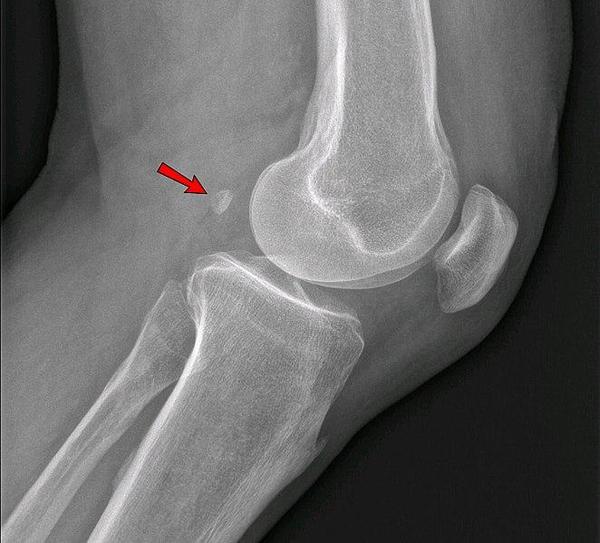

7. What is the anatomical finding in this knee xray?

Correct Answer: fabella

This finding is a fabella which is a normal finding on xray and is a sesamoid bone embedded in a tendon on the posterior aspect of the knee.